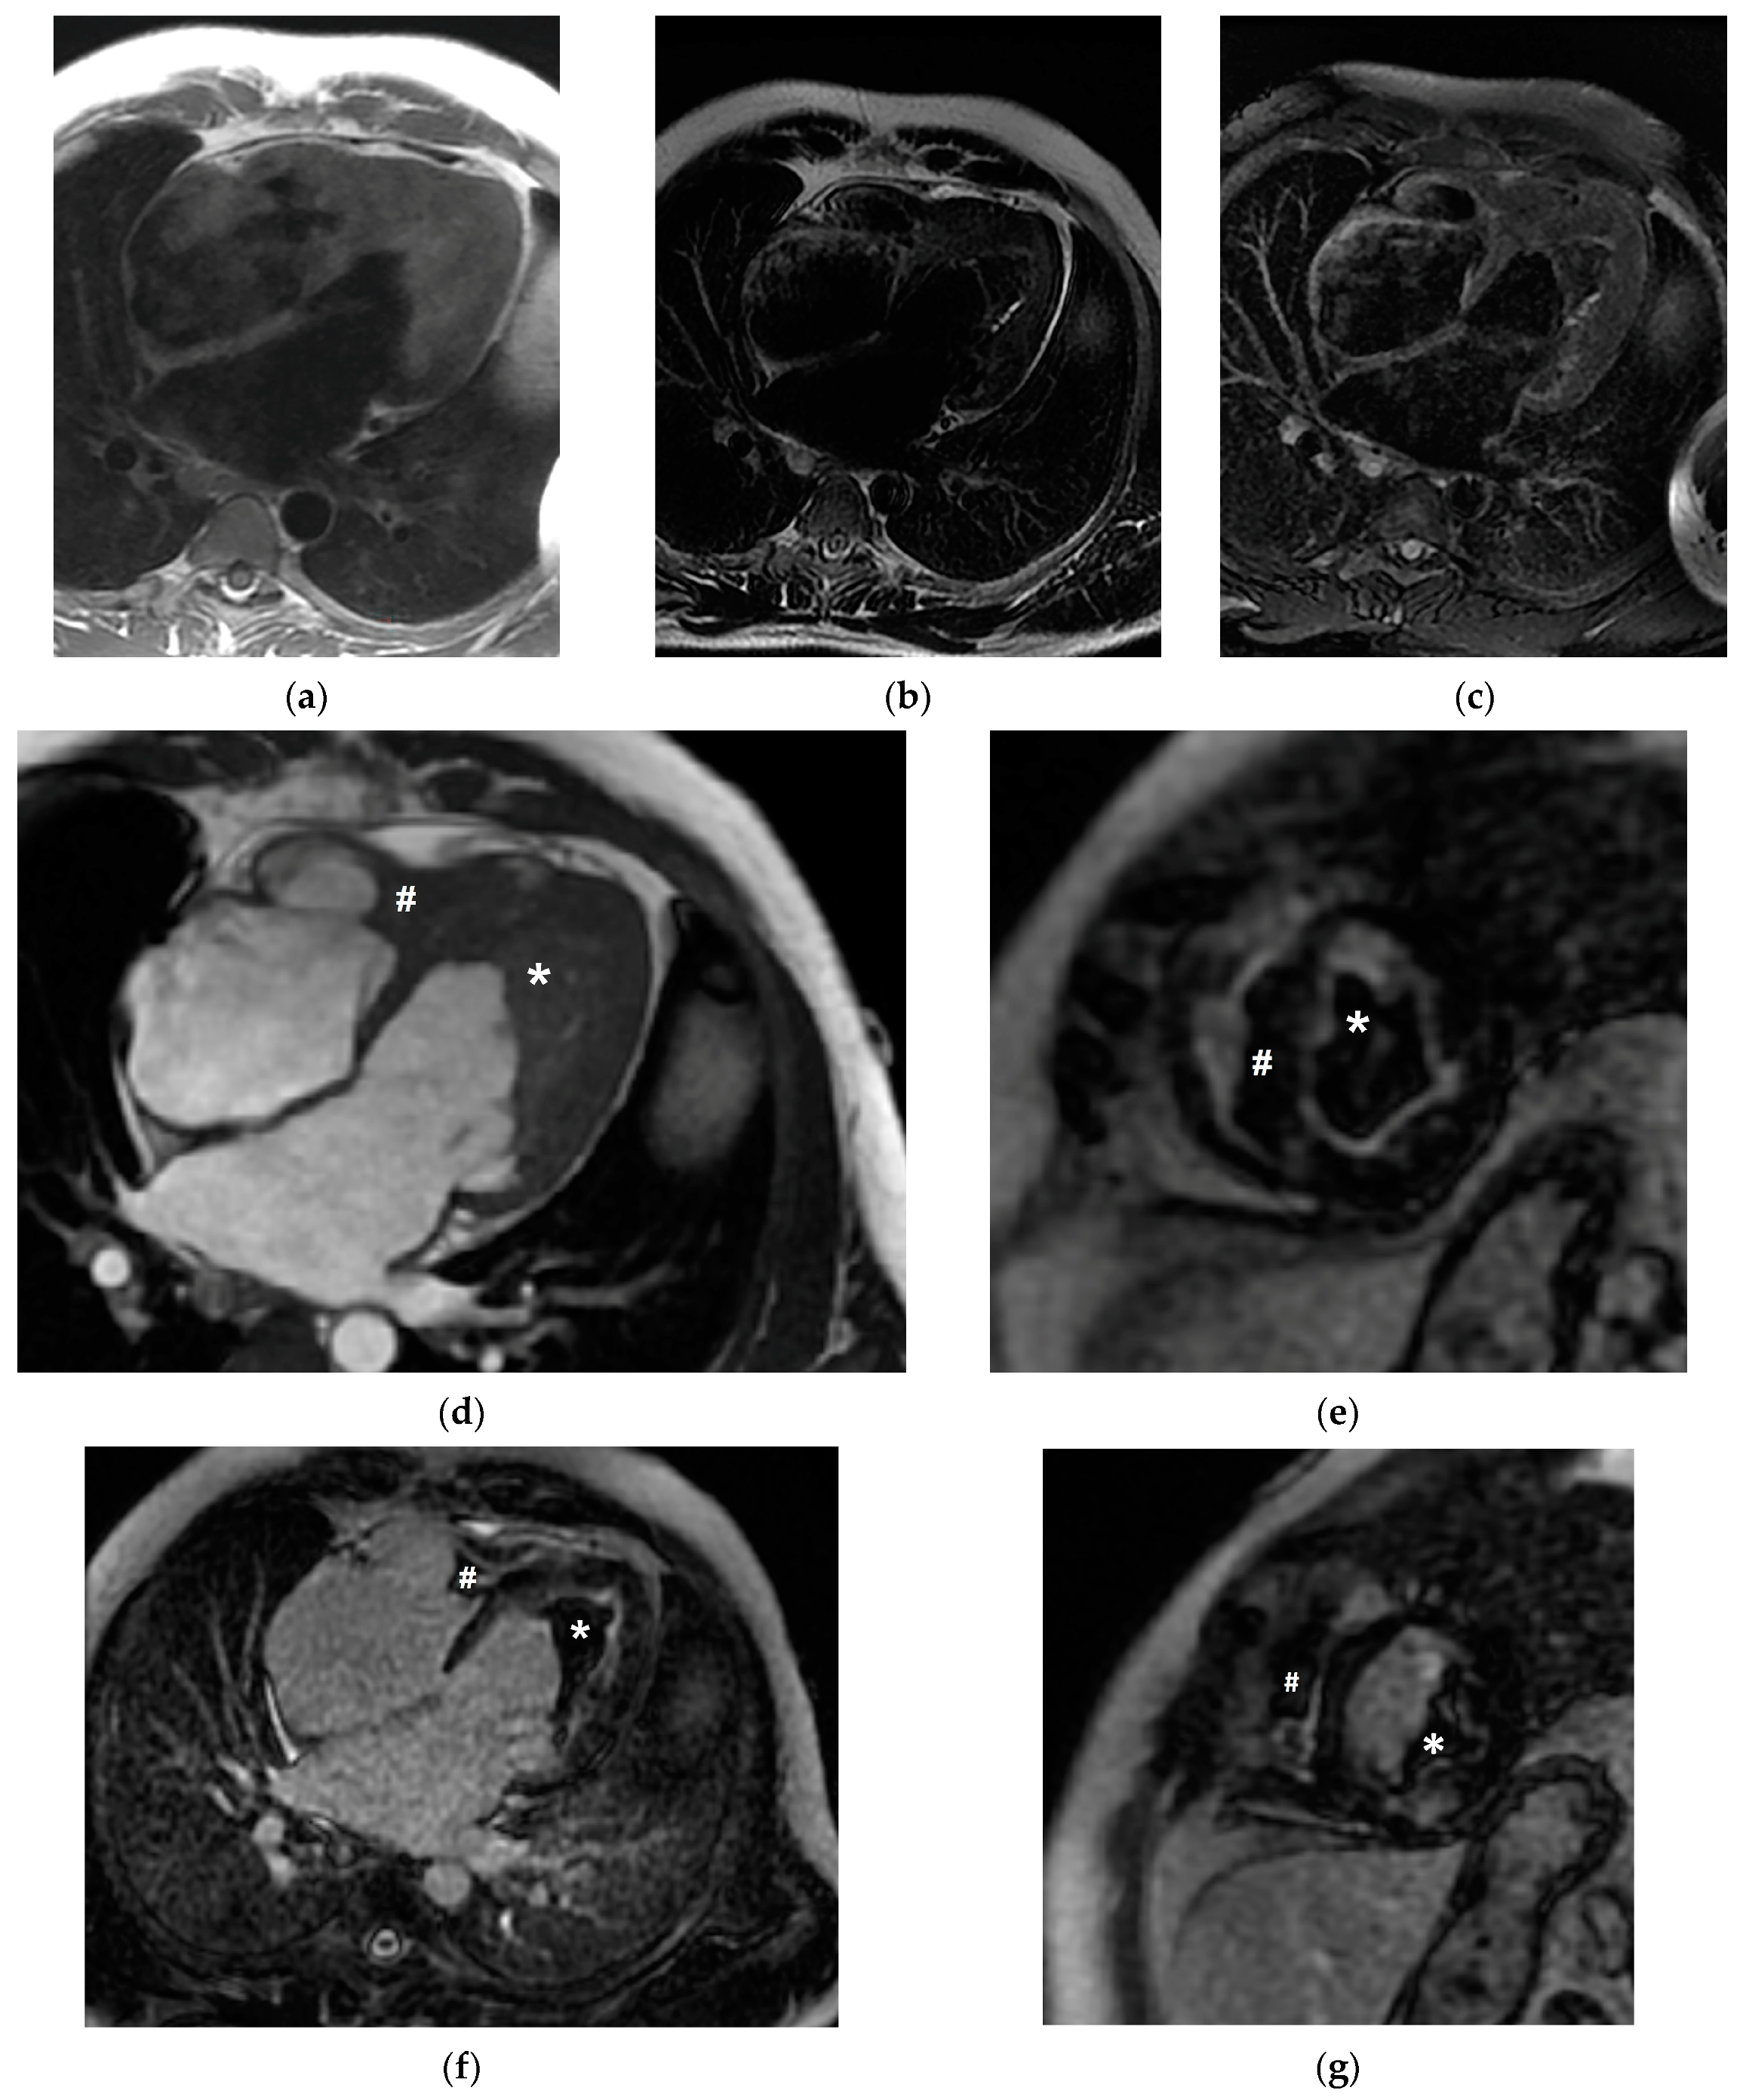

2. Case Presentation

3. Discussion